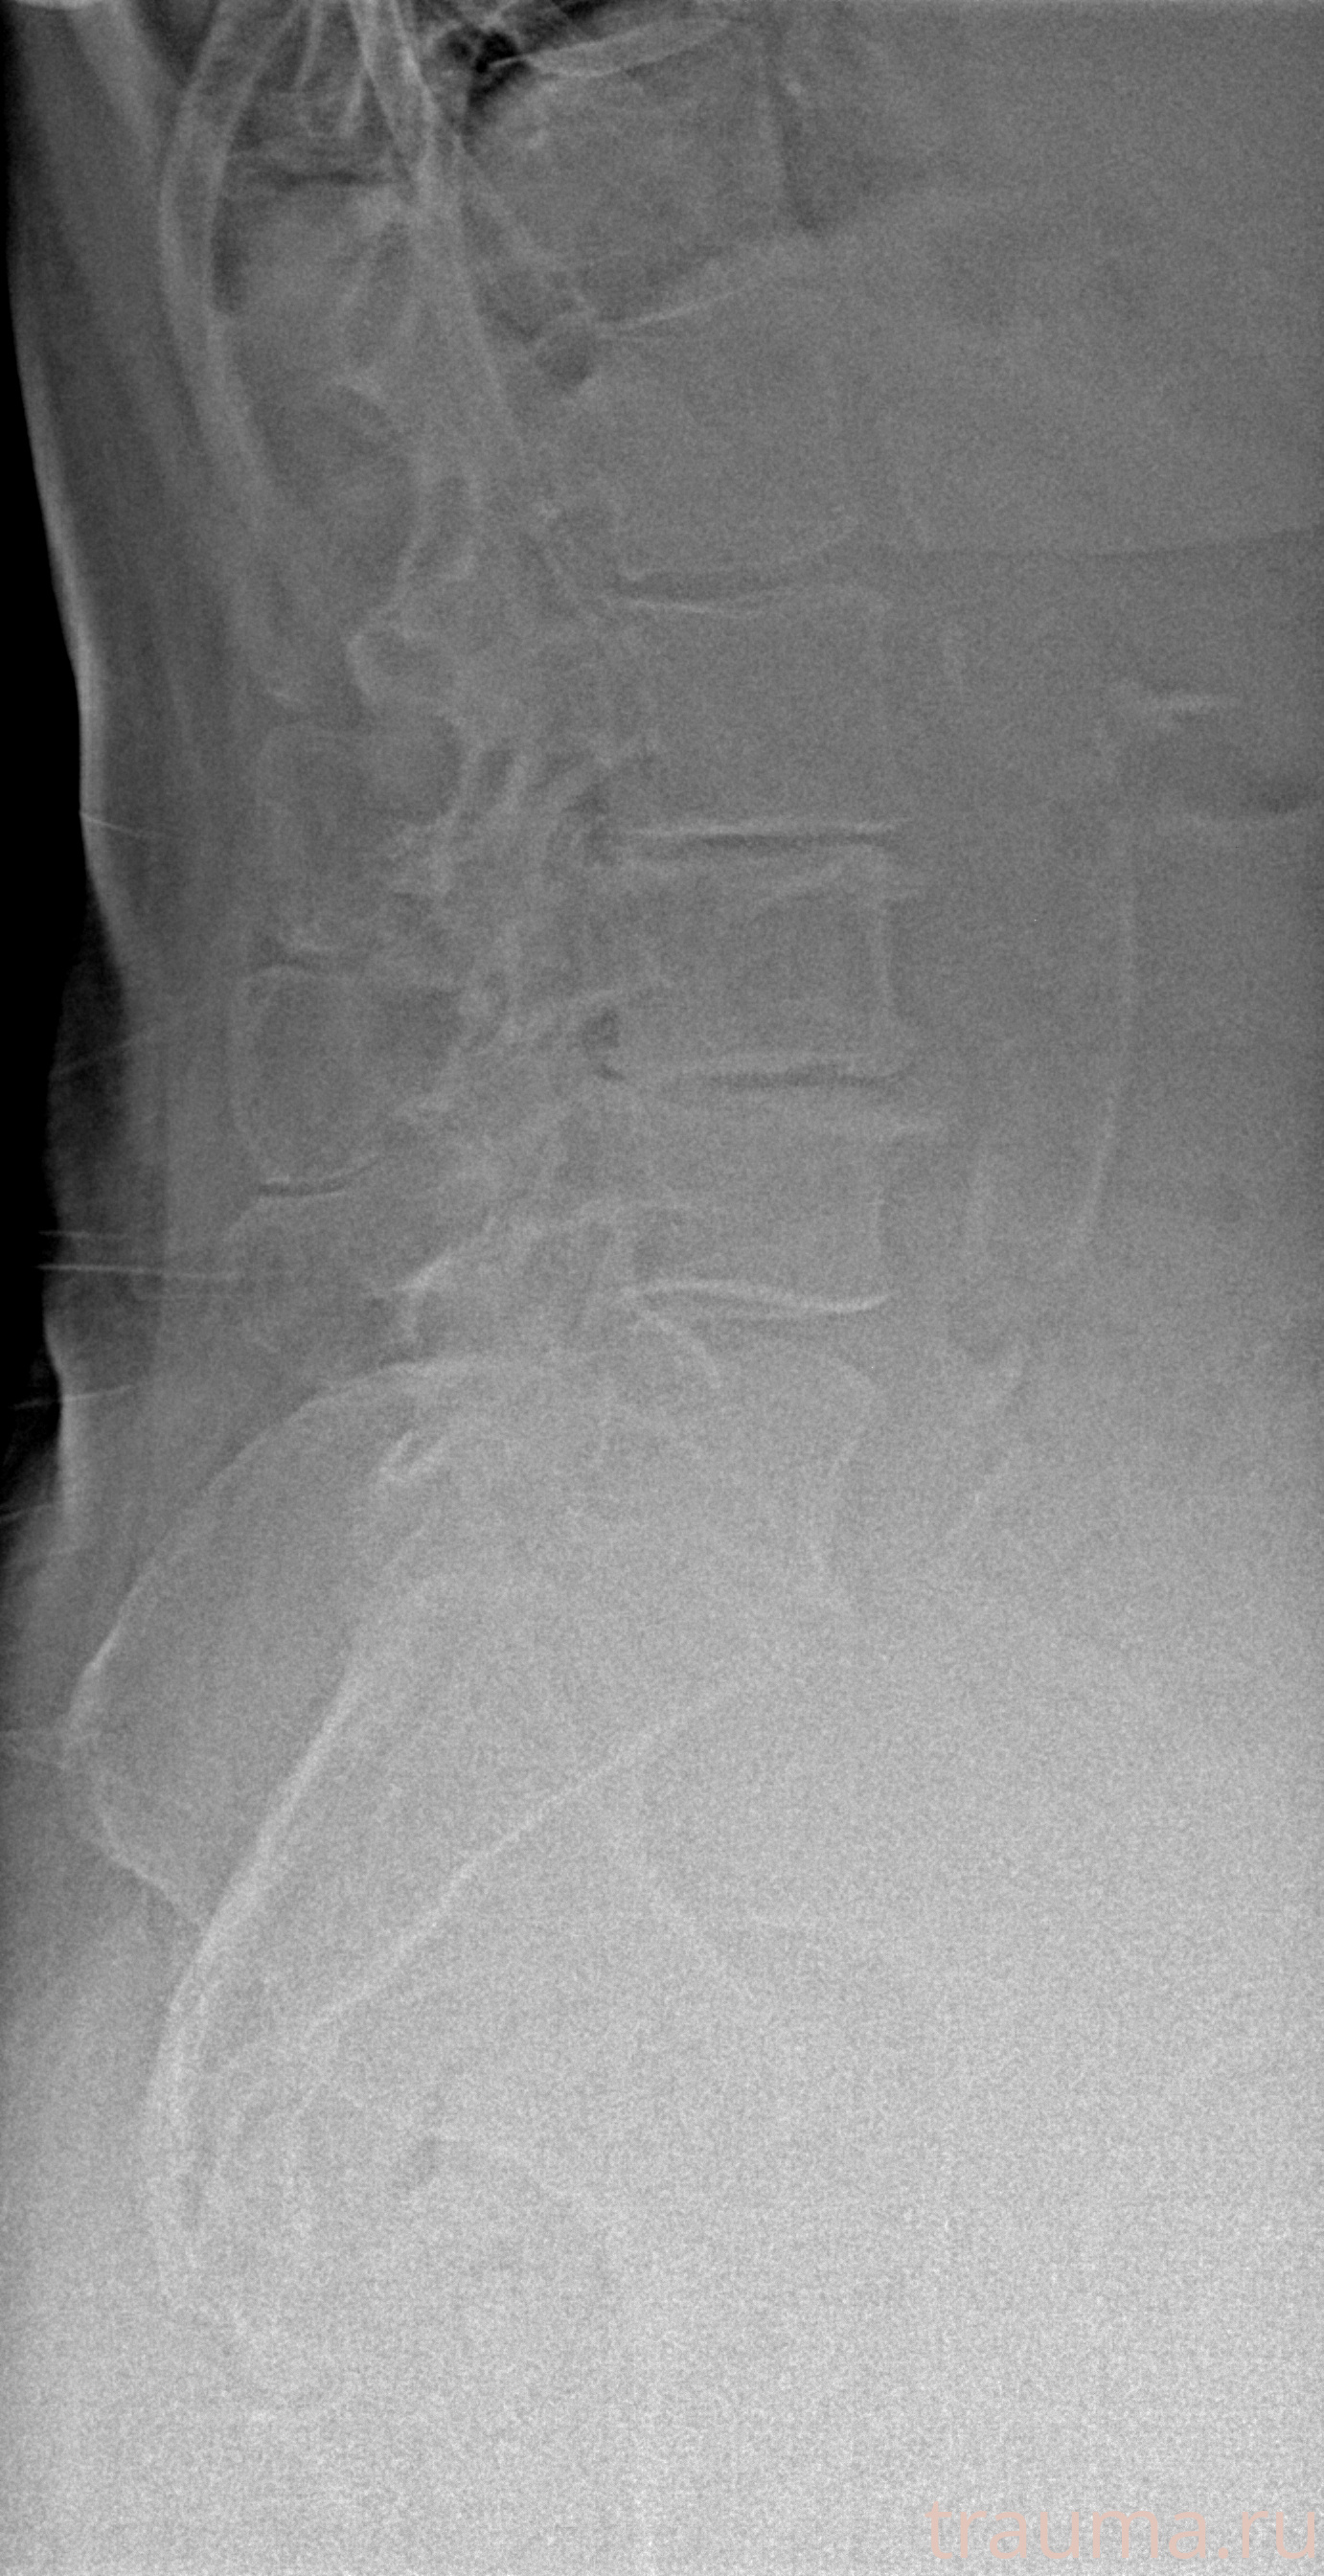

Рентген на дому: по вашему адресу приезжает врач-рентгенолог, травматолог-ортопед с мобильным рентгеновским аппаратом, проводит диагностику травмы или заболевания, делает необходимые рентгенограммы, дает рекомендации по дальнейшему лечению. Получить качественные снимки в домашних условиях возможно благодаря уникальной методике, разработанной МосРентген Центром для института  Склифосовского

при переломе шейки бедра и пневмонии от компании МосРентген Центр - партнера Института имени Склифосовского